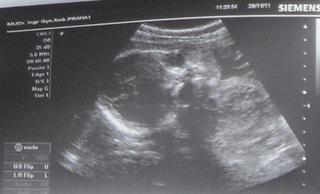

@kokorunecka vies co neviem ci som dobre pochopila lebo asi som neprecitala vsetky prispevky tvoje ale ja mam tiez malinke babetko.ja som bola na USG v 31tt a tiez ma len 1200g takze idem znova pred vianocami ci sa to upravuje lebo aj mateo sa narodil 2570g v 39tt.